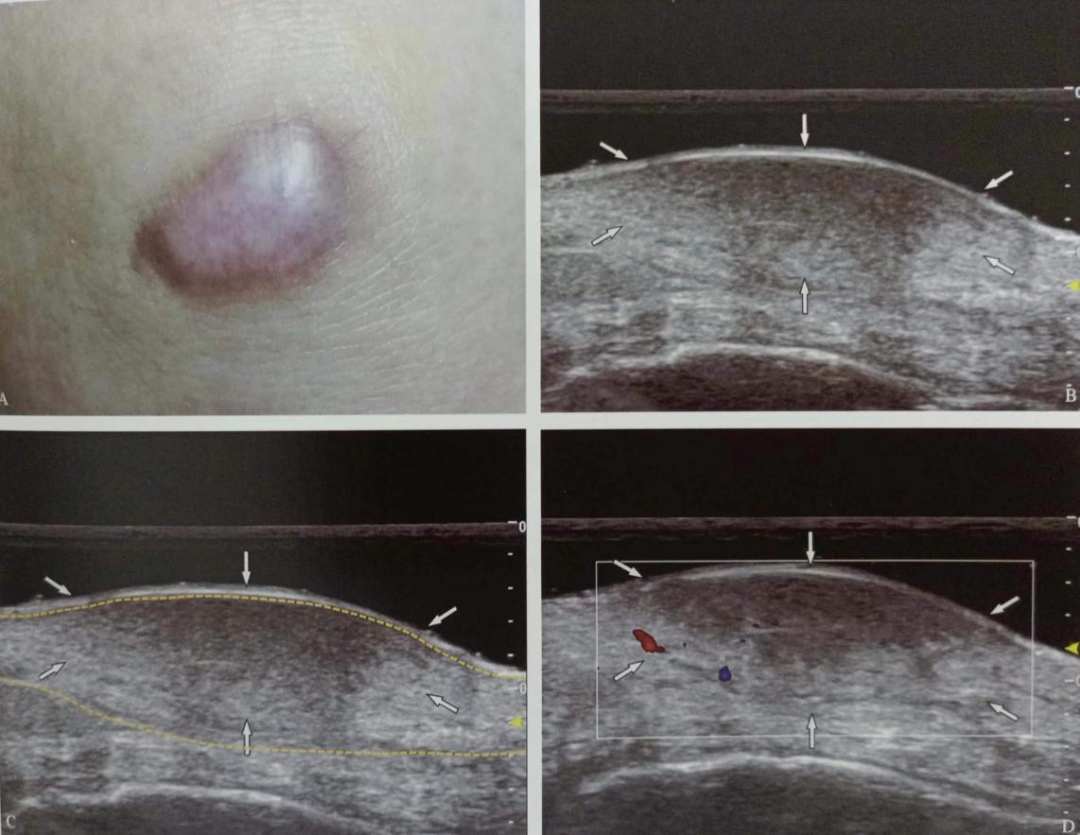

如:表皮樣囊腫、淺表脂肪瘤、色素痣、毛母質(zhì)瘤、皮膚纖維瘤、血管平滑肌瘤、血管球瘤等。

圖片

表皮樣囊腫